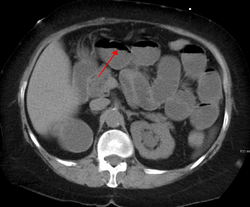

Small bowel obstruction on ultrasound[19]

The main diagnostic tools are blood tests, X-rays of the abdomen, CT scanning, and ultrasound. If a mass is identified, biopsy may determine the nature of the mass.[citation needed]

Radiological signs of bowel obstruction include bowel distension and the presence of multiple (more than six) gas-fluid levels on supine and erect abdominal radiographs. Ultrasounds may be as useful as CT scanning to make the diagnosis.[17]

Contrast enema or small bowel series or CT scan can be used to define the level of obstruction, whether the obstruction is partial or complete, and to help define the cause of the obstruction. The appearance of water-soluble contrast in the cecum on an abdominal radiograph within 24 hours of it being given by mouth predicts resolution of an adhesive small bowel obstruction with sensitivity of 97% and specificity of 96%.[18]